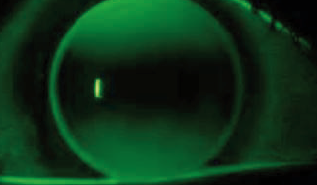

Corriger un astigmatisme est à l’heure actuelle plus facile grâce à l’amélioration du design et du système de stabilisation des lentilles souples, aux nouveaux matériaux tant en lentille souple qu’en lentille rigide perméable à l’oxygène (LRPO) – l’adaptation restant toujours délicate dans les fortes puissances.